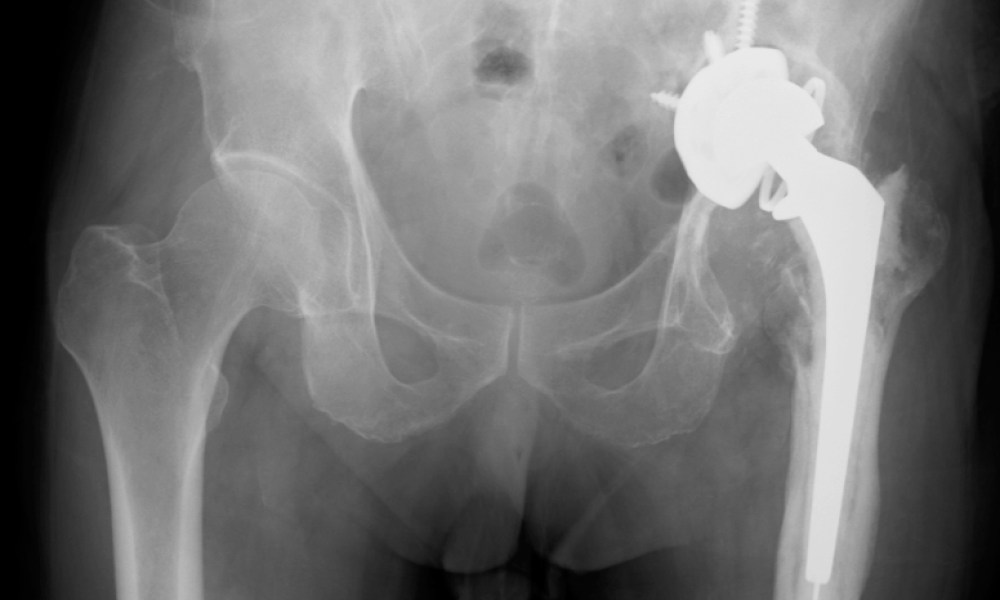

Pelvic X-ray of the patient with left hip pain.

On the X-ray, it is apparent that the left acetabulum has virtually been destroyed and the implant has actually entered the pelvic space. The left femur also looks both “moth-eaten” and hypertrophic, with new bone formation around the implant (compare with the right femur).

In this case, the patient has developed chronic left prosthetic hip implant infection. There was also a sinus tract which cannot be seen from the X-ray.